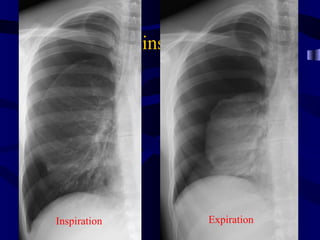

Tension Pneumothorax

ptxinspexp

Inspiration                Expiration